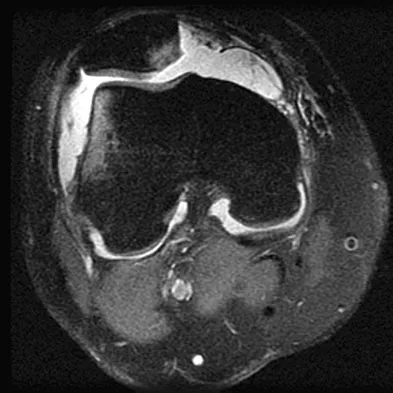

A 28-year-old man reports knee stiffness, swelling, and a constant ache that is worse with activity. Examination reveals an effusion, global tenderness, and warmth to the touch. Flexion is limited to 110 degrees. Figures 48a through 48d show sagittal T1-weighted, sagittal T2-weighted, axial T1-weighted fat-saturated gadolinium, and axial gradient echo MRI scans. Based on these findings, what is the most likely diagnosis?

Explanation